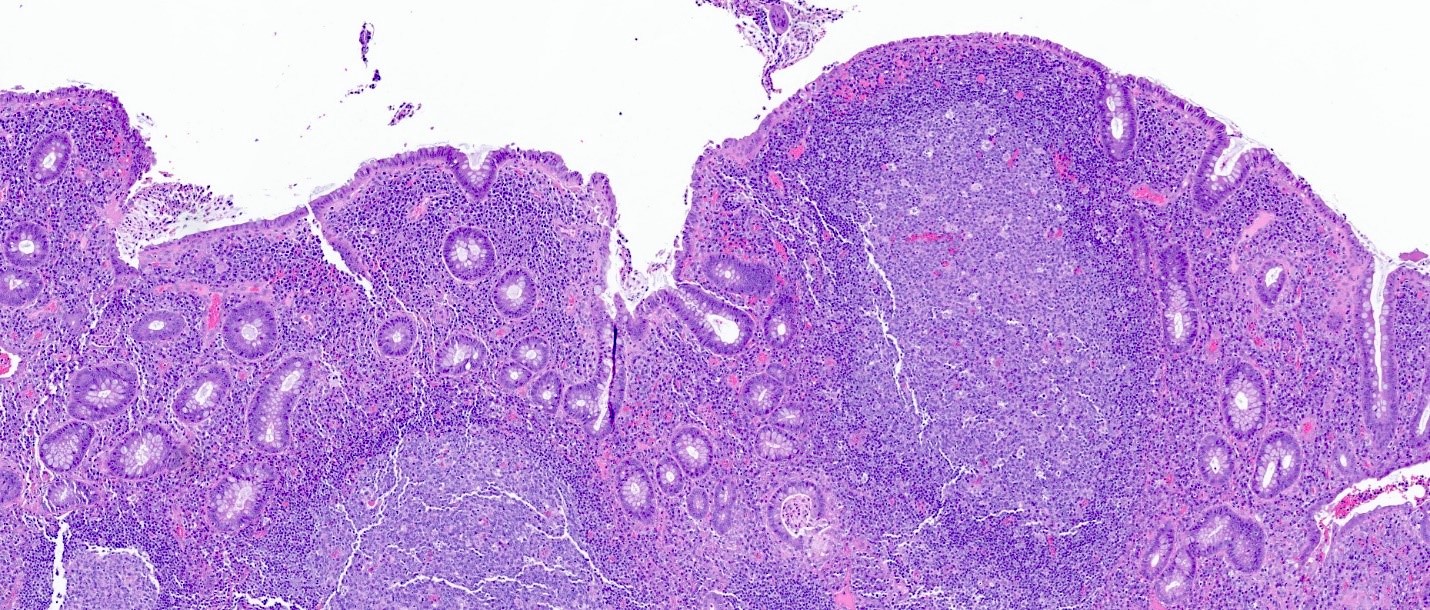

Microscopic (histologic) images

Contributed by Catherine E. Hagen, M.D. and Dustin W. Parsons, M.D.

Lymphoid aggregate and architectural changes

Microscopic (histologic) description

• Lymphoid follicular hyperplasia with germinal centers

• Muscularis mucosa hypertrophy, which is often patchy

• Architectural changes with distortion of crypts, crypt branching and loss of crypts

• Degenerative mucosal surface epithelium with cell exfoliation and pyknotic nuclei

• Loss of goblet cells and mucin

• Mucosal ulceration with granulation tissue

• Varying degrees of inflammation, with features of both activity (neutrophil predominant) and chronicity (lymphoplasmacytic)

• Focal edema

• Pseudopolyps

• Paneth cell metaplasia

• References: Hum Pathol 2022;123:31, World J Gastroenterol 2018;24:1734, Histopathology 1991;19:55